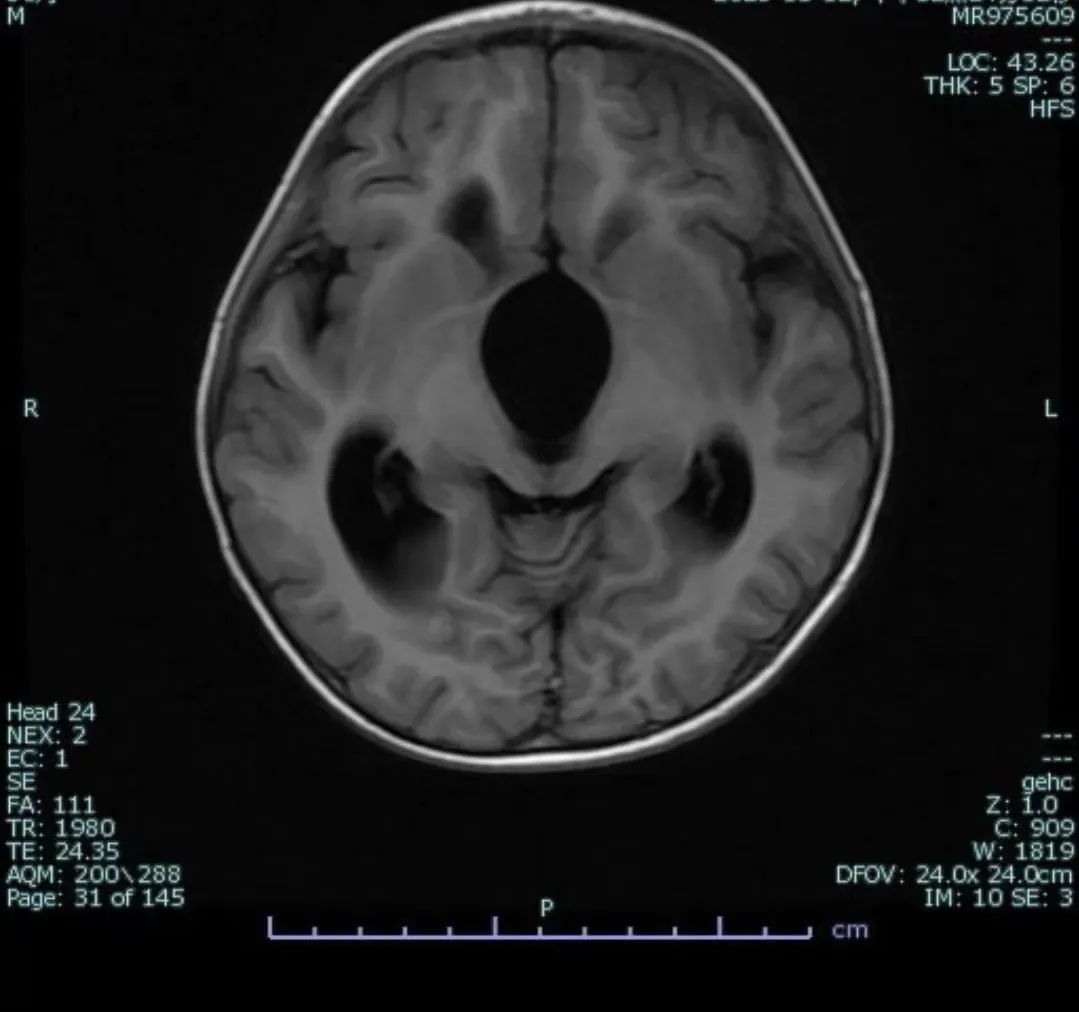

心急如焚的家长急匆匆来到了郑州大学第三附属医院(河南省妇幼保健院)神经外科。主任医师 张云鹤对悠悠进行了仔细检查后,指着片子对家属说:“看这张片子的构图像不像个‘米老鼠’?正常的片子是不会呈现这种影像的。这两个‘米老鼠’的耳朵,是扩大的侧脑室额角,‘米老鼠’的大鼻子(脸),是囊肿不断长大后,被其撑大的三脑室,这是典型的鞍上池囊肿的影像学表现。”